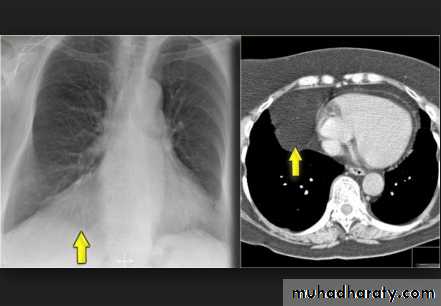

Encapsulated fluid

(A) PA and (B) lateral chest radiographs. Pleural fluid is encapsulated in the major fissure and against the anterior chest wall. These encysted fluid collections can mimic a lung tumour.